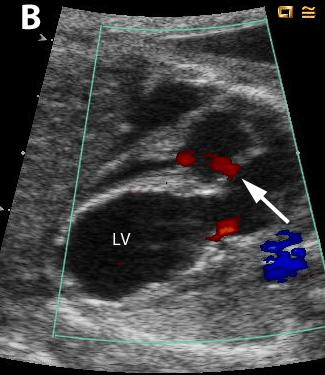

Η τροποποίηση των πρώιμων αυτών τεχνικών επέτρεψε από τότε τις επεμβάσεις με διαδερμική πρόσβαση και χρήση καθετήρων, και γνώρισε τεχνική επιτυχία όχι μόνο στη στένωση της εμβρυϊκής αορτικής βαλβίδας, αλλά και στην στένωση και ατρησία των βαλβίδων της πνευμονικής αρτηρίας, καθώς και στο σύνδρομο της υποπλαστικής αριστερής καρδιάς (HLHS) με άτρητο ή πολύ περιορισμένα ανοικτό μεσοκολπικό διάφραγμα. [13, 14]

Οι αναφορές για την κλινική πορεία των μωρών, που υπεβλήθησαν σε αυτές τις επεμβάσεις, όπως δίνονται από τις μεγαλύτερες σειρές αυτών των επεμβάσεων, επιβεβαιώνουν την τεχνική τους επιτυχία και την αναπαραγωγιμότητα. [15, 16] Υποδεικνύουν, επίσης, ότι οι επιτυχείς εμβρυϊκές επεμβάσεις οδηγούν σε βελτιωμένη λειτουργική ανάπτυξη των κοιλιών και του μυοκαρδίου, ενώ το έμβρυο παραμένει ακόμη στη μήτρα.

Άλλα επιστημονικά Κέντρα έχουν επίσης αναπαράγει τις αρχικές επιτυχίες [17,18], και τα στοιχεία που αποδεικνύουν ότι η βαλβιδοπλαστική του εμβρύου, που πάσχει από ατρησία ή στένωση των βαλβίδων της αορτής ή της πνευμονικής αρτηρίας, μπορεί να διευκολύνει την ικανότητα διεξαγωγής της κυκλοφορίας και από τις δύο κοιλίες μετά τη γέννηση, ενώ η διαφραγματοπλαστική για τα άτρητα ή με σοβαρό περιορισμό μεσοκολπικά διαφράγματα, μπορεί να βελτιώσει τη μεταγεννητική κυκλοφορική σταθερότητα και τις πιθανότητες επιβίωσης μετά την αρχική ανακουφιστική χειρουργική επέμβαση. [19, 20]